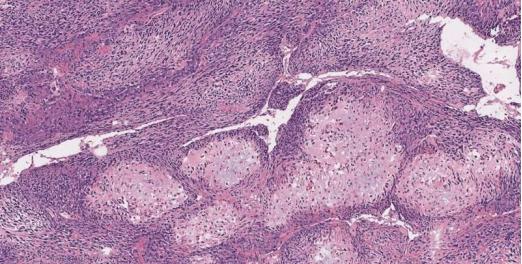

靠溶解,是确定一块骨头是否含有癌细胞最原始传统的方法。首先,骨头块会被从人体内移除然后送到实验室,在那里其坚硬的钙基质会被慢慢溶解,只留下活细胞。然后,医生会对其余材料进行切片和成像操作。由于该过程可能需要一到七天才能完成,非常耗时,医生在手术过程中不能依靠它来确定肿瘤周围和附近骨骼的健康状况,因此他们往往会切掉一些不该切掉的骨组织,这对患者的健康来说是不利的。

相比之下,加州理工学院研发的新成像技术显得更为优越。该成像技术,被称为实时3D轮廓扫描紫外光声显微镜技术或UV-PAM,旨在取代传统的识别癌性骨组织的方法。UV-PAM的工作原理是使用激光使活组织中的分子振动,这些振动以超声波频率发生,可将组织和器官快速成像,就像用超声波看婴儿彩超一样。由于该过程只需几分钟,因此它使医生能够在手术时及时将健康骨骼与癌骨区分开来。